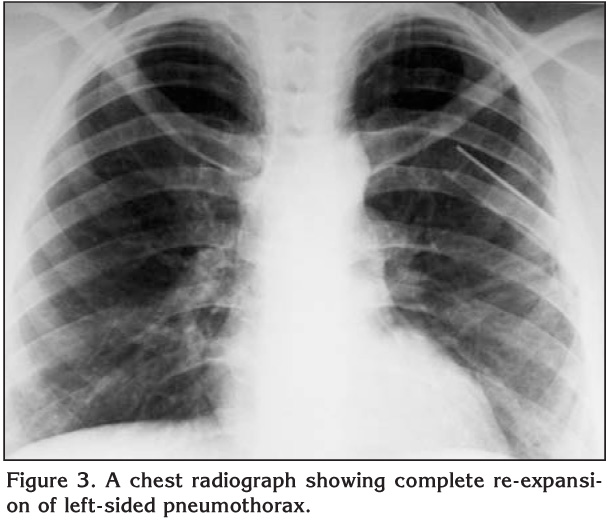

Pneumothorax In Pregnancy Secondary To Ruptured Pulmonary ...

Pregnancy is quite uncommon, with only 56 cases chest X-ray showed incomplete lung expansion. Patient was assessed by the Obstetrician and obstetrical repeated chest X-ray showed fully expanded lungs. The chest tubes were removed. ... Retrieve Content